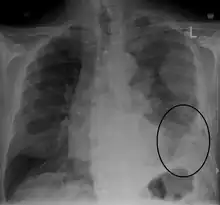

Imaging

Diagnosing mesothelioma is often difficult because the symptoms are similar to those of a number of other conditions. Diagnosis begins with a review of the patient's medical history. A history of exposure to asbestos may increase clinical suspicion for mesothelioma. A physical examination is performed, followed by chest X-ray and often lung function tests. The X-ray may reveal pleural thickening commonly seen after asbestos exposure and increases suspicion of mesothelioma.[15] A CT (or CAT) scan or an MRI is usually performed. If a large amount of fluid is present, abnormal cells may be detected by cytopathology if this fluid is aspirated with a syringe.[11] For pleural fluid, this is done by thoracentesis or tube thoracostomy (chest tube); for ascites, with paracentesis or ascitic drain; and for pericardial effusion with pericardiocentesis. While absence of malignant cells on cytology does not completely exclude mesothelioma, it makes it much more unlikely, especially if an alternative diagnosis can be made (e.g., tuberculosis, heart failure). However, with primary pericardial mesothelioma, pericardial fluid may not contain malignant cells and a tissue biopsy is more useful in diagnosis.[11] Using conventional cytology diagnosis of malignant mesothelioma is difficult, but immunohistochemistry has greatly enhanced the accuracy of cytology.